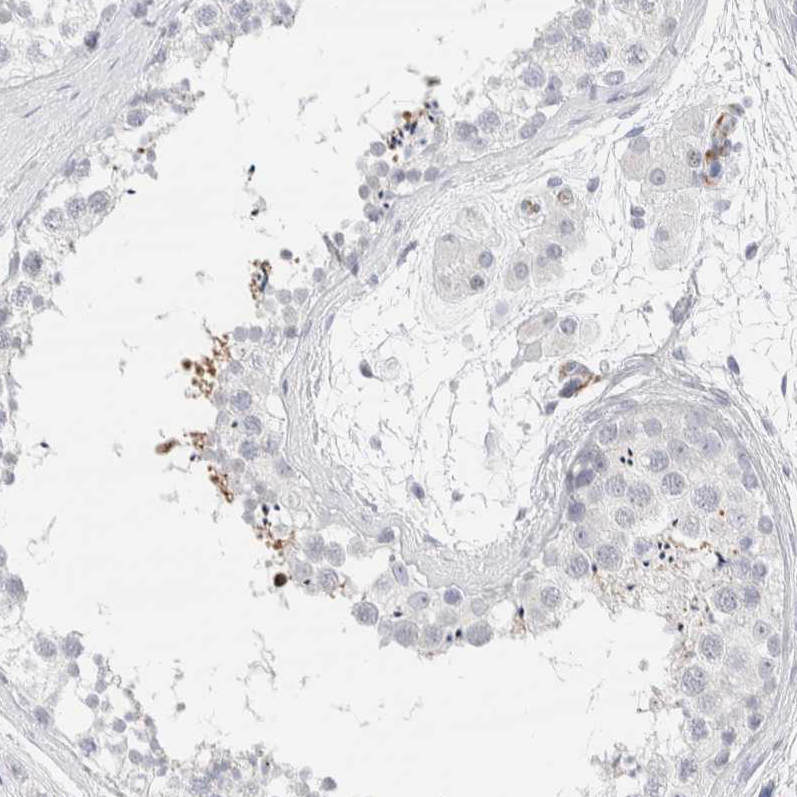

Immunohistochemistry analysis in human cerebral cortex and pancreas tissues using HPA022905 antibody. Corresponding SEPT4 RNA-seq data are presented for the same tissues.